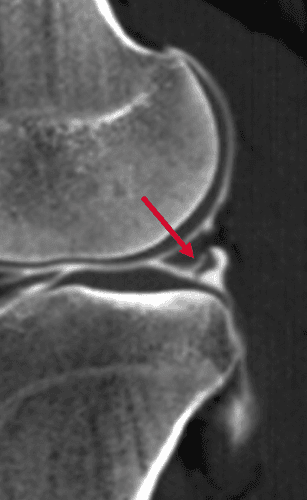

Apport de l'arthroscanner dans la recherche de fissure méniscale en complément de l'IRM

MRICT